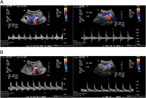

Conservative management of a traumatic common iliac venous pseudoaneurysm: a case report

Walker Lyons and others

Journal of Surgical Case Reports, Volume 2017, Issue 5, May 2017, rjx085, https://doi.org/10.1093/jscr/rjx085